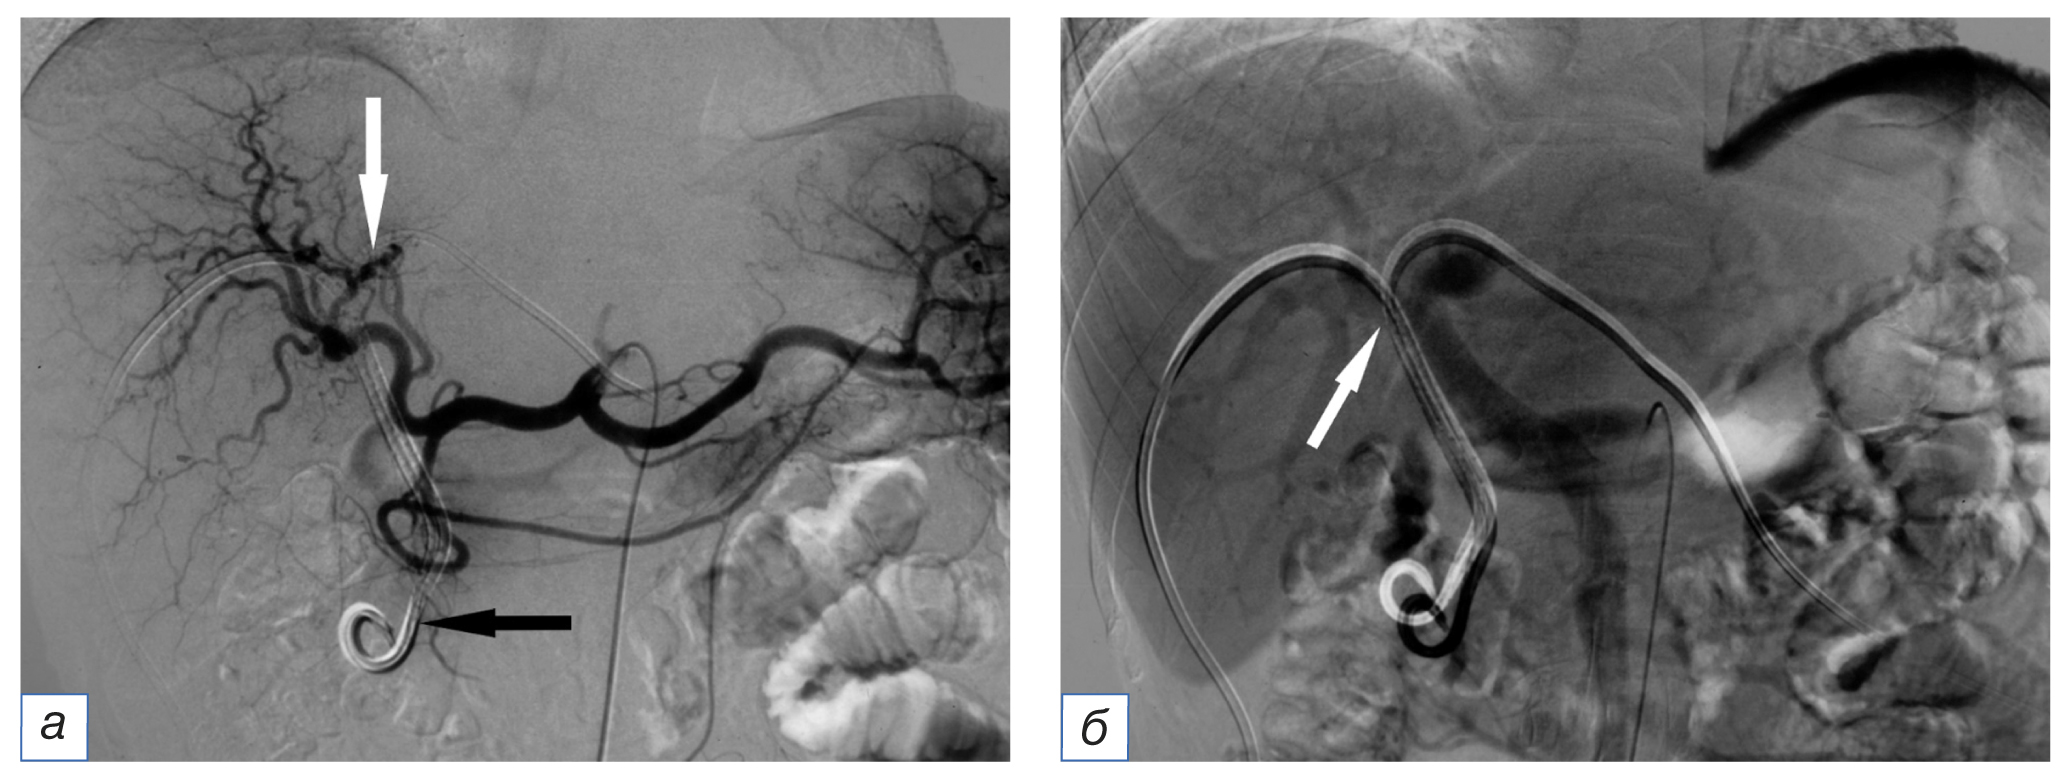

После диагностического этапа выполняли ФДТ. Использовали световод с прямым выходом излучения, проведенный на глубину 3 мм в светооптический гель проксимальной части цилиндрического диффузора. Таким образом, торцевой поток света преобразовывался в сферический и обеспечивал равномерное облучение всей внутренней поверхности опухолевой стриктуры. Диффузор устанавливали в желчные протоки по пункционному каналу, параллельно проводнику. Если геометрия доступа не позволяла провести систему облучения в место обструкции, то по проводнику заводили интродьюсер 11F, и диффузор проводили через него (рис. 1).

Рис. 1. Холангиография у пациента с опухолью Клацкина, Bismuth IV: а — визуализируются стриктура общего печеночного и обоих долевых желчных протоков (черная стрелка), установлены два билатеральных наружно-внутренних холангиодренажа (белые стрелки); б — дренажи удалены по проводникам; проводится внутрипротоковая фотодинамическая терапия правым доступом. Рабочая часть диффузора находится в зоне стриктуры (стрелки). / Fig. 1. Patient with Klatskin tumor, Bismuth IV, cholangiography: а — stricture of the right and left hepatic ducts (black arrow); in the projection of the bile ducts, two external-internal cholangiodrainages are visualized (white arrow); б — drainages are removed on the guides; photodynamic therapy with right access is performed. The working part of the diffuser is located in the stricture zone (arrow).